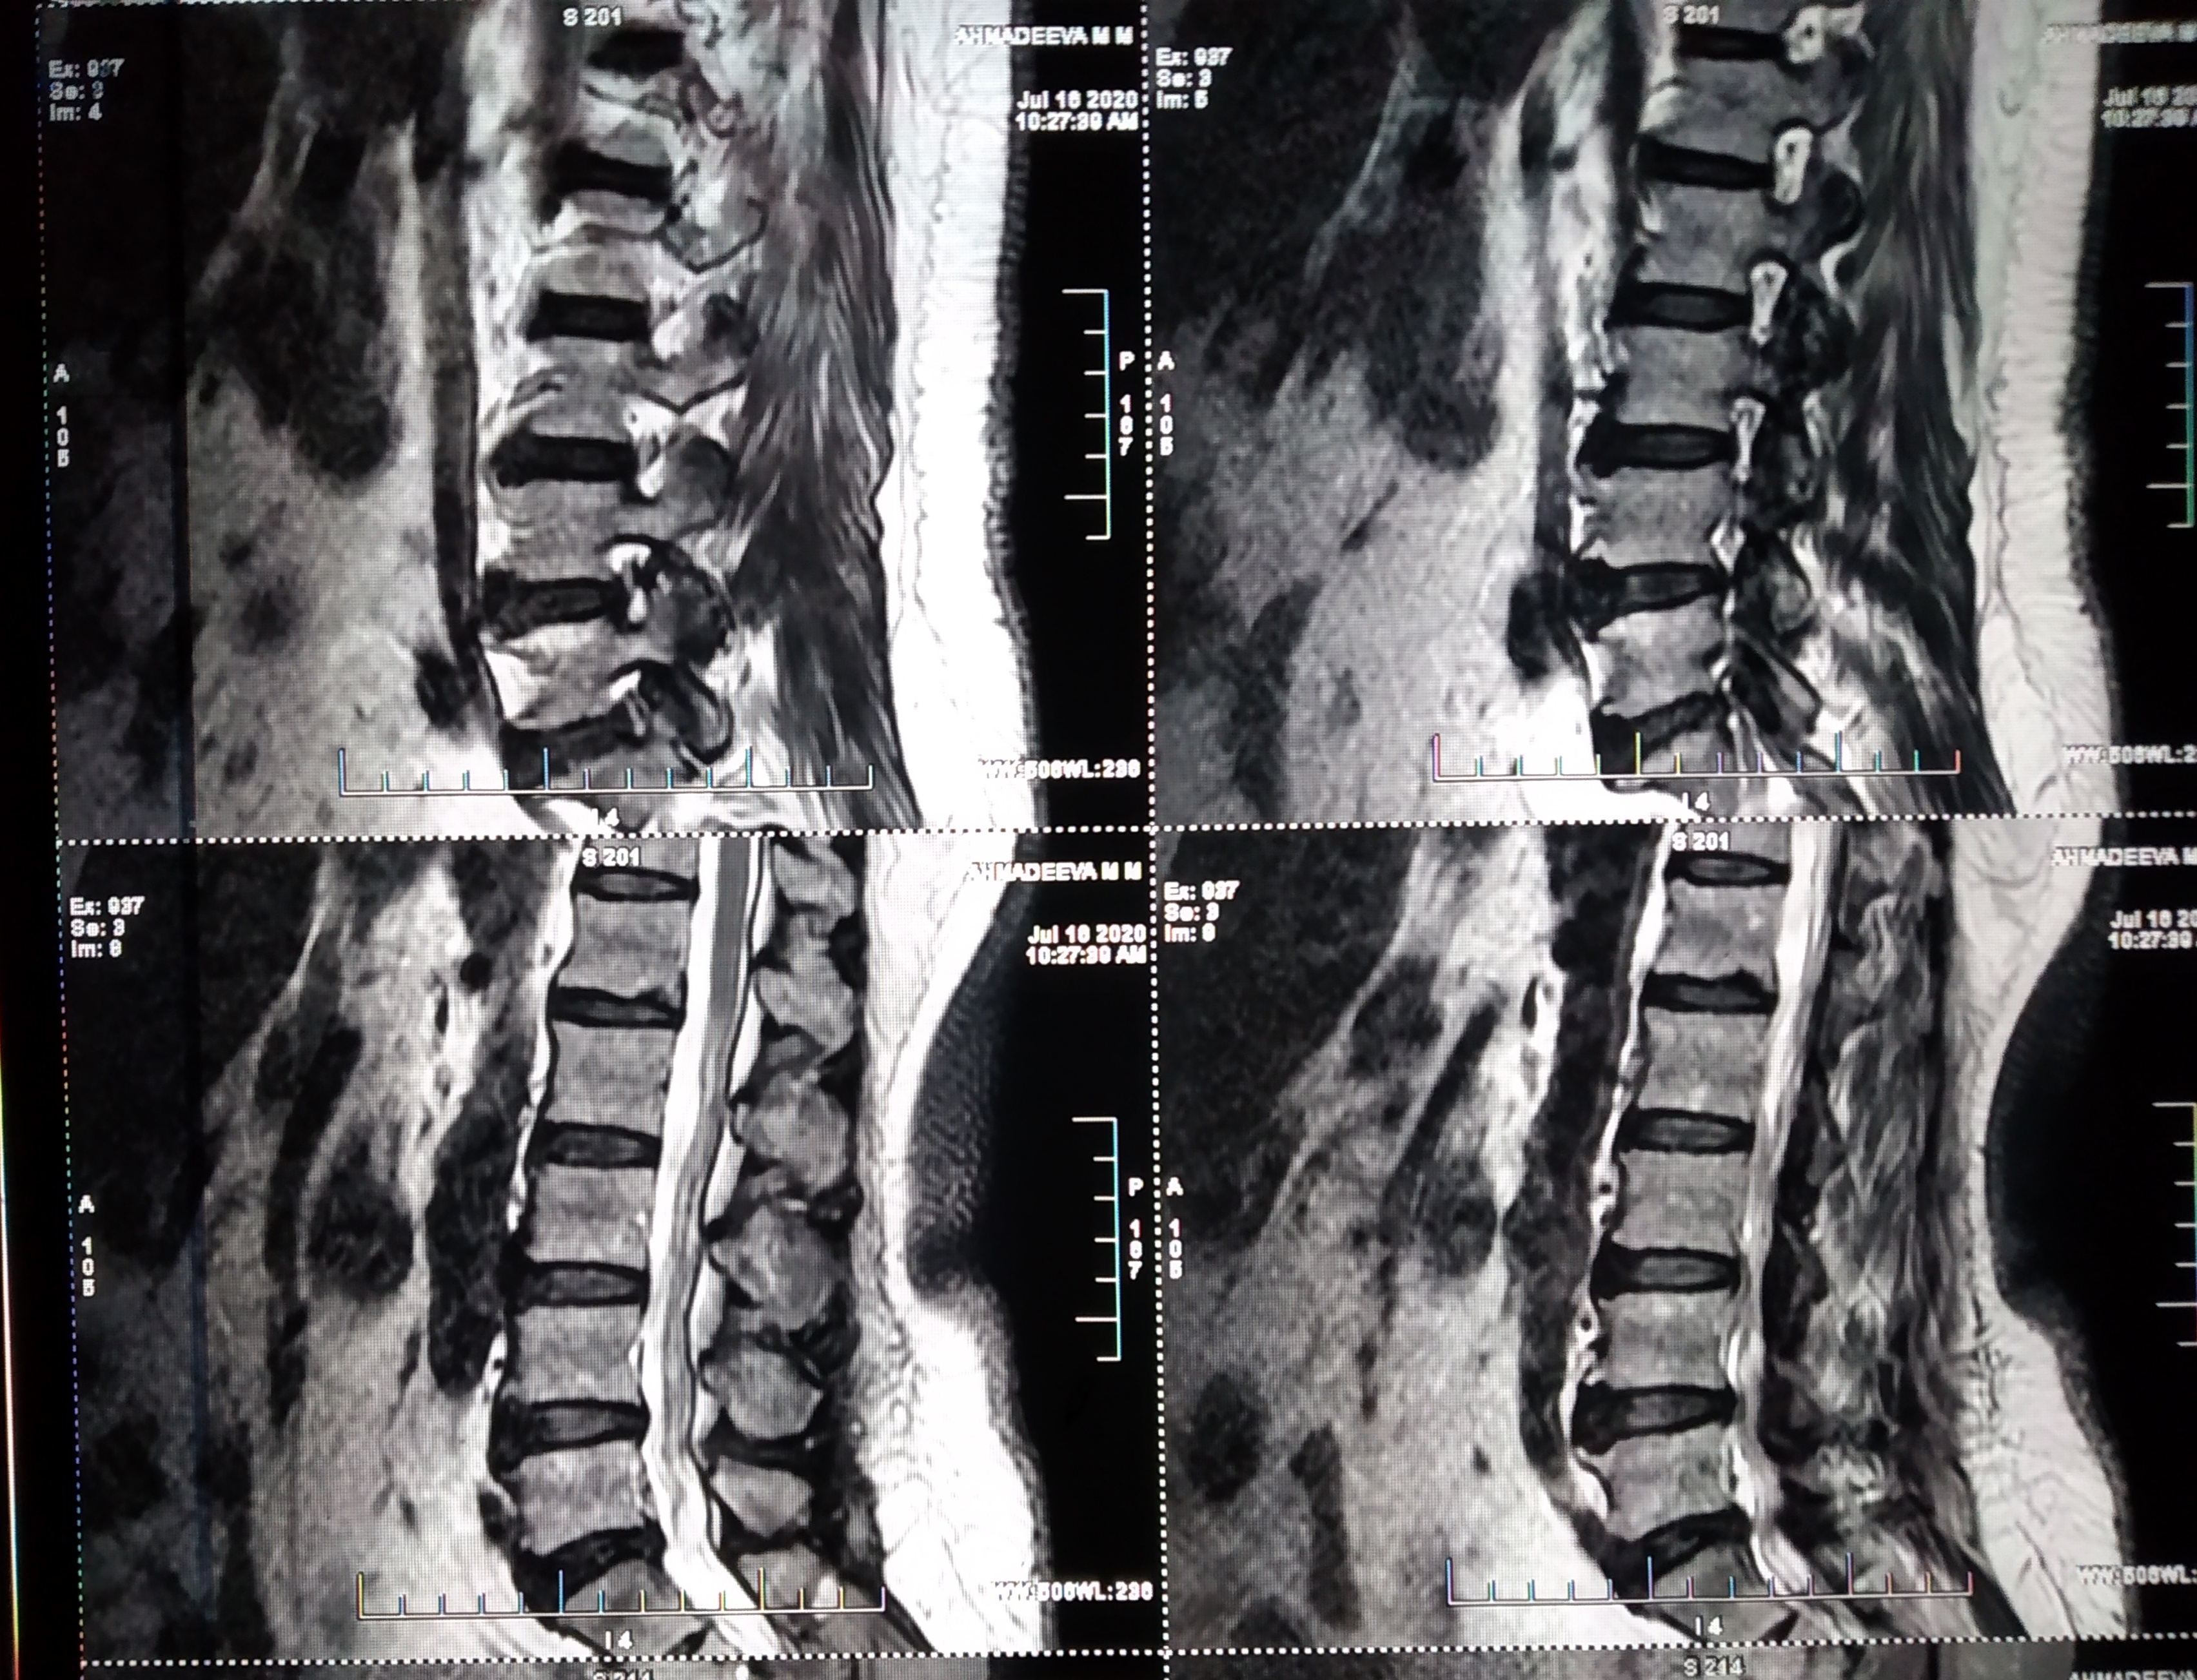

Отделы позвоночника для мрт схема фото и названия